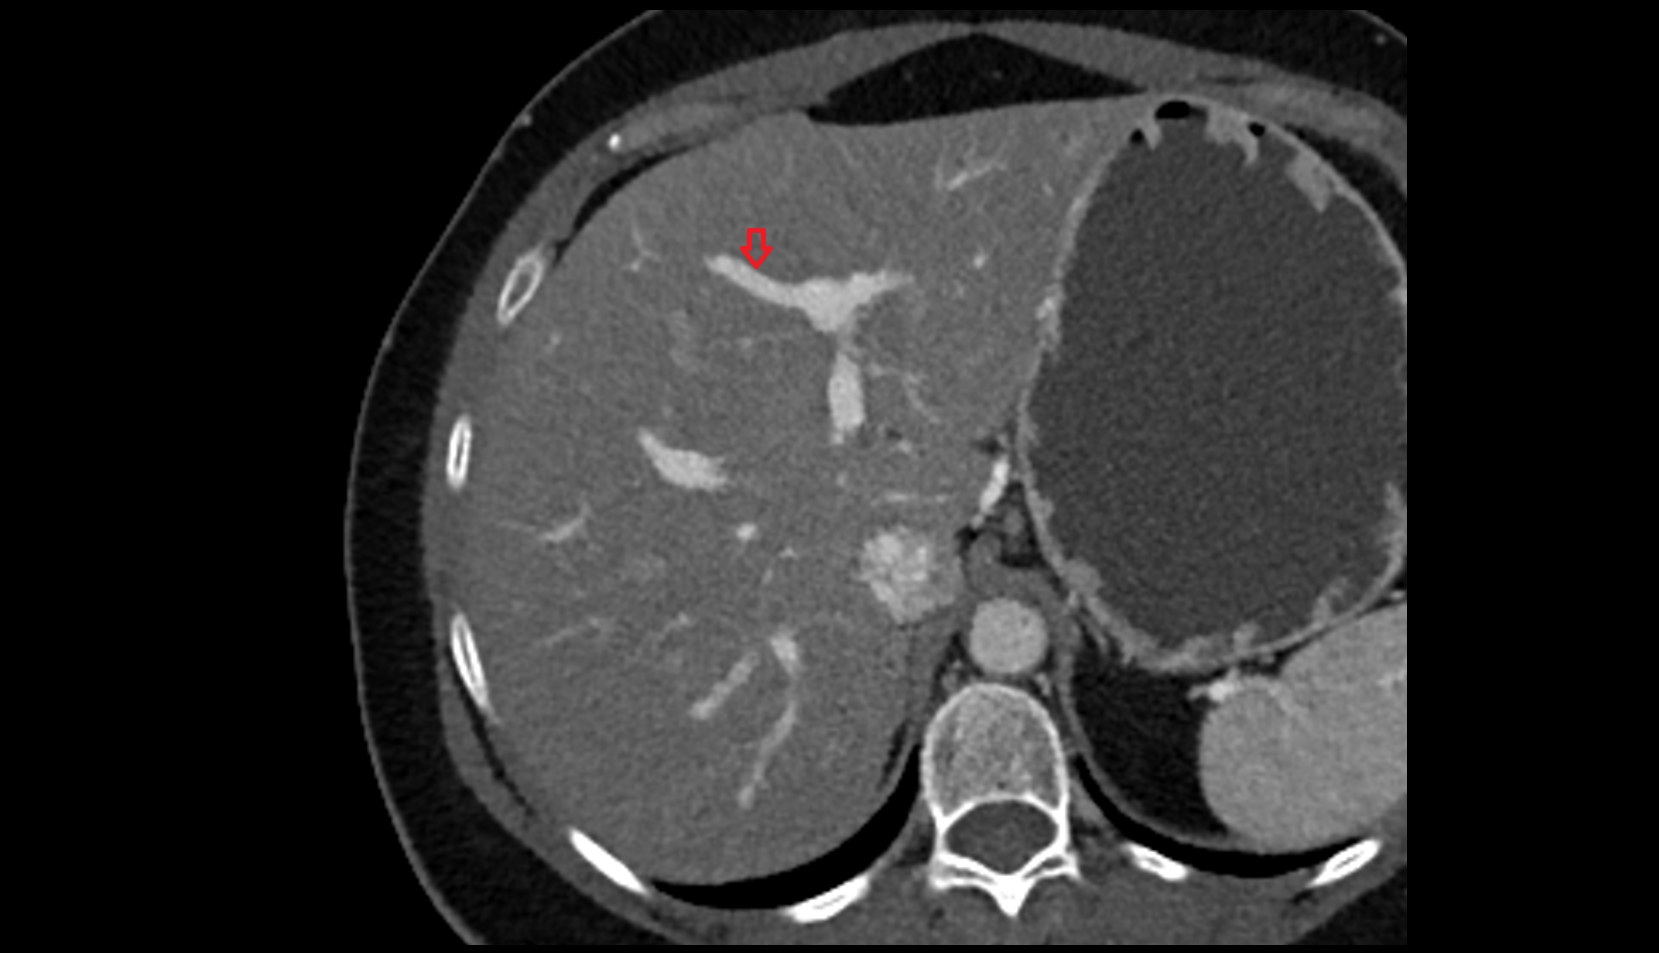

- Liver

- Left lobe of liver

- Right lobe of liver